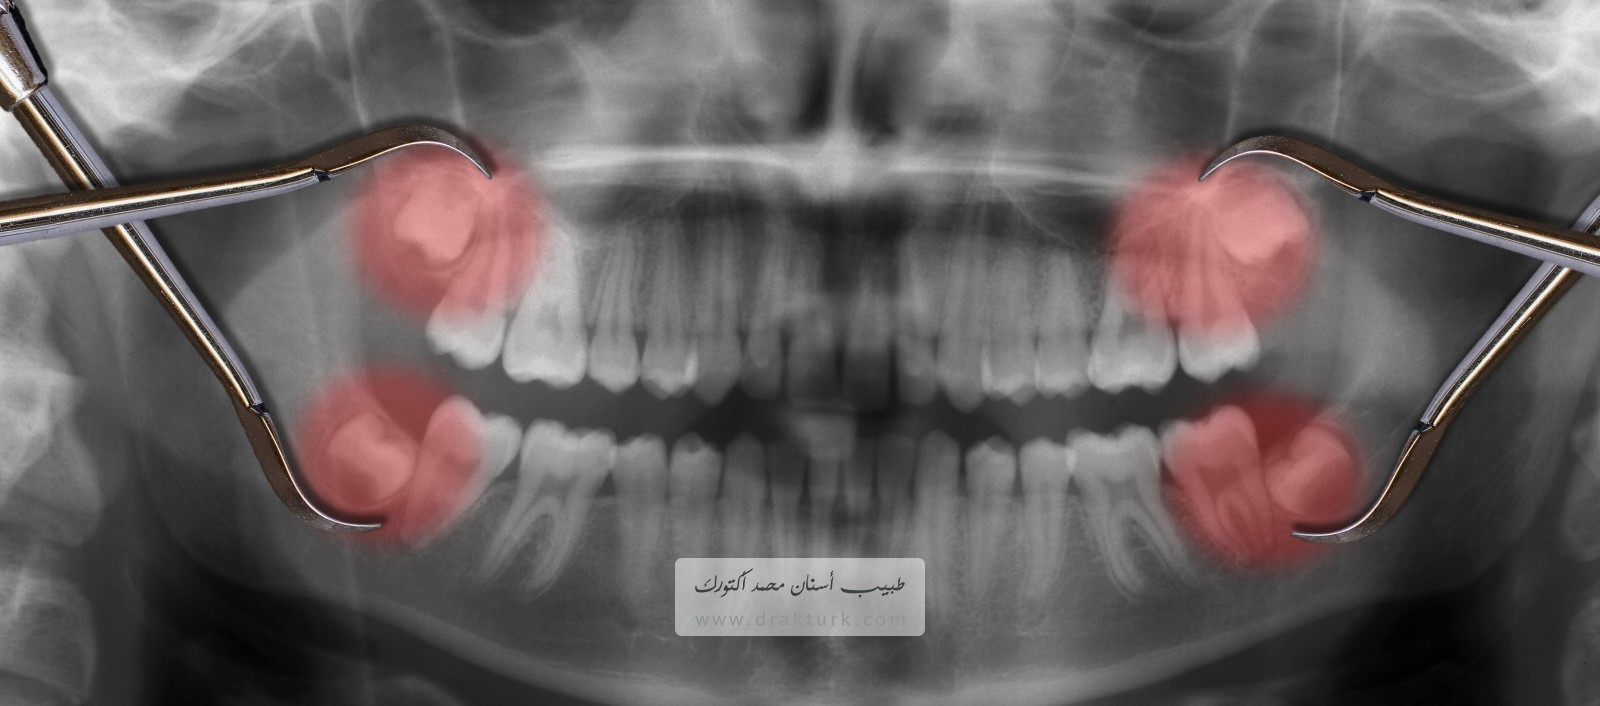

قلع ضرس العقل هو إجراء جراحي لإزالة ضرس عقل أو أكثر؛ ويقصد بذلك الضروس الأربعة الدائمة التي تنبت لدى البالغين الموجودة في الأركان الخلفية من الفم بأعلاه وبأسفله.

إذا لم يكن لدى أحد ضروس العقل مساحة للنمو (ضرس عقل مطمور) وأدى ذلك إلى ألم أو عدوى أو غيرها من المشاكل بالأسنان، يُرجح أنك ستقتلعه. يجوز إجراء جراحة قلع ضرس العقل عن طريق طبيب أسنان أو جراح فم.

ينمو للعديد من الأفراد ضروس عقل متأثرة — ضروس لا يوجد لها متسع كافي لتنبثق داخل الفم أو لتنمو بشكل طبيعي. قد لا تنبثق ضروس العقل المطمورة (الدفينة) إلا انبثاقًا جزئيًا، أو لا تنبثق على الإطلاق.